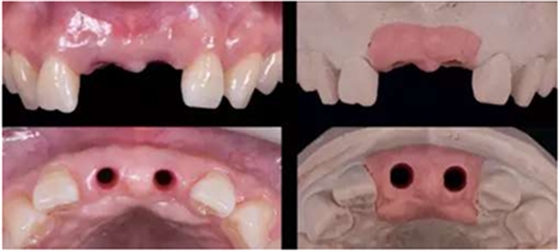

種植過(guò)渡義齒制作:

制取種植模型:由種植醫(yī)生制取種植模型,隨后交給技工室行種植過(guò)渡義齒制作。

蠟型制作完成后,翻制硅橡膠導(dǎo)板,根據(jù)穿齦輪廓來(lái)修整人工牙齦,保證修整后鄰緣的位置與診斷蠟型一致。即根據(jù)硅橡膠導(dǎo)板及齦緣修整牙齦范圍,隨后進(jìn)行穿齦輪廓的修整。

修復(fù)種植臨時(shí)基臺(tái)

本病例選用光固化樹(shù)脂材料制作過(guò)渡義齒,光固化樹(shù)脂材料豐富,方便操作,戴牙出現(xiàn)問(wèn)題時(shí),也方便及時(shí)進(jìn)行修復(fù)。

種植過(guò)渡義齒完成(螺絲固位)

通過(guò)使用個(gè)性化轉(zhuǎn)移桿進(jìn)行取模,模型精確復(fù)制牙齦輪廓

11,21 ASC 全瓷基臺(tái)一體冠蠟型